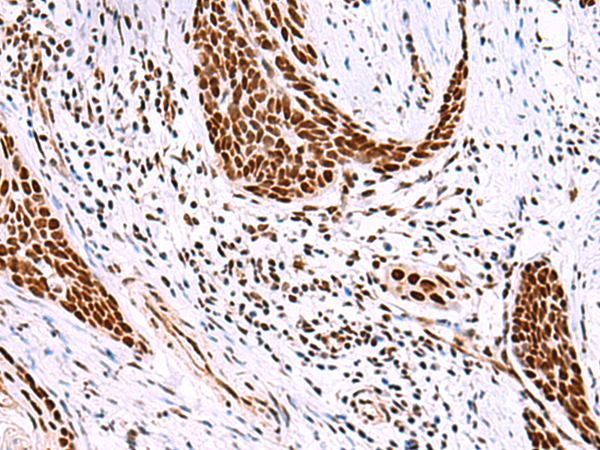

| IHC | 1/40-1/200 | Human,Mouse,Rat |

Antibodies against ISY1 or RAB43 individually are used in immunohistochemistry, Western blotting, or immunofluorescence to study their localization, expression levels, or functional roles. However, the ISY1-RAB43 antibody’s exact application depends on its design—whether it detects a fusion product, simultaneous expression, or co-localization. Researchers utilize such tools to investigate molecular mechanisms in cellular models or disease contexts, aiming to identify therapeutic targets or biomarkers. Further studies are needed to fully characterize the ISY1-RAB43 interaction and its biological significance.